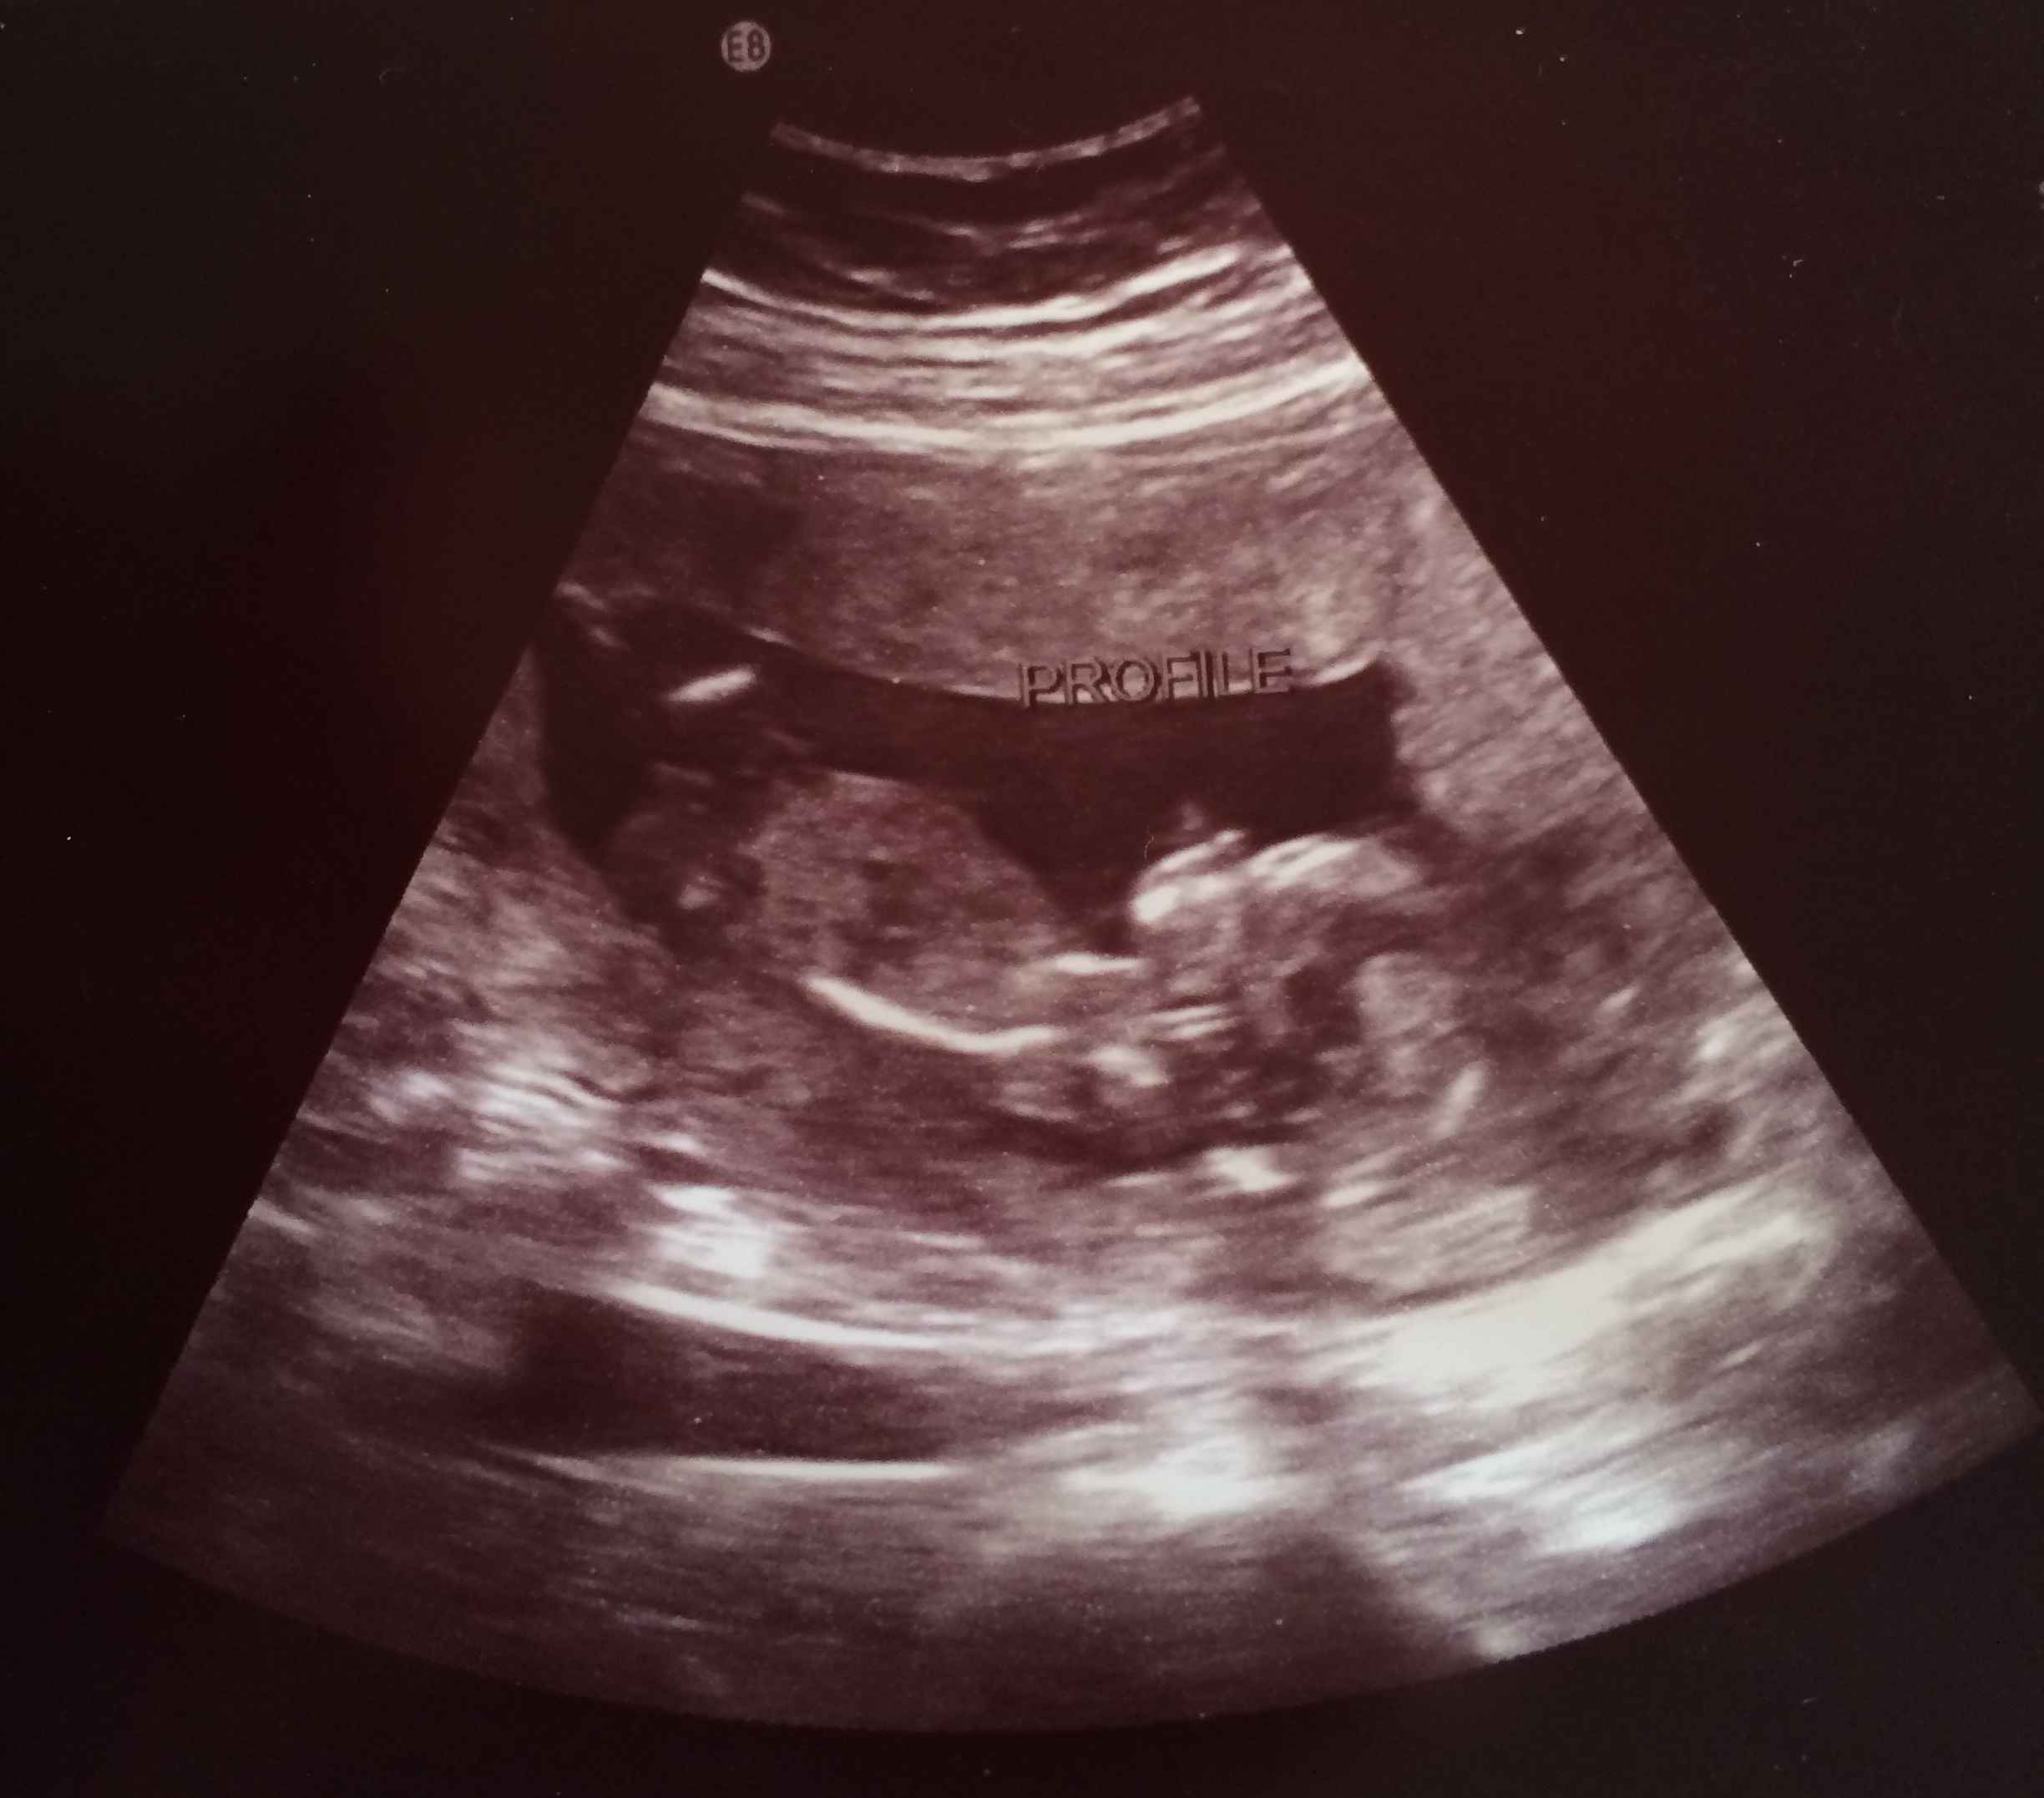

This one is at 10 weeks and was done transabdominally. Based on skull theory, I would think this is a boy.

Attachment 15967